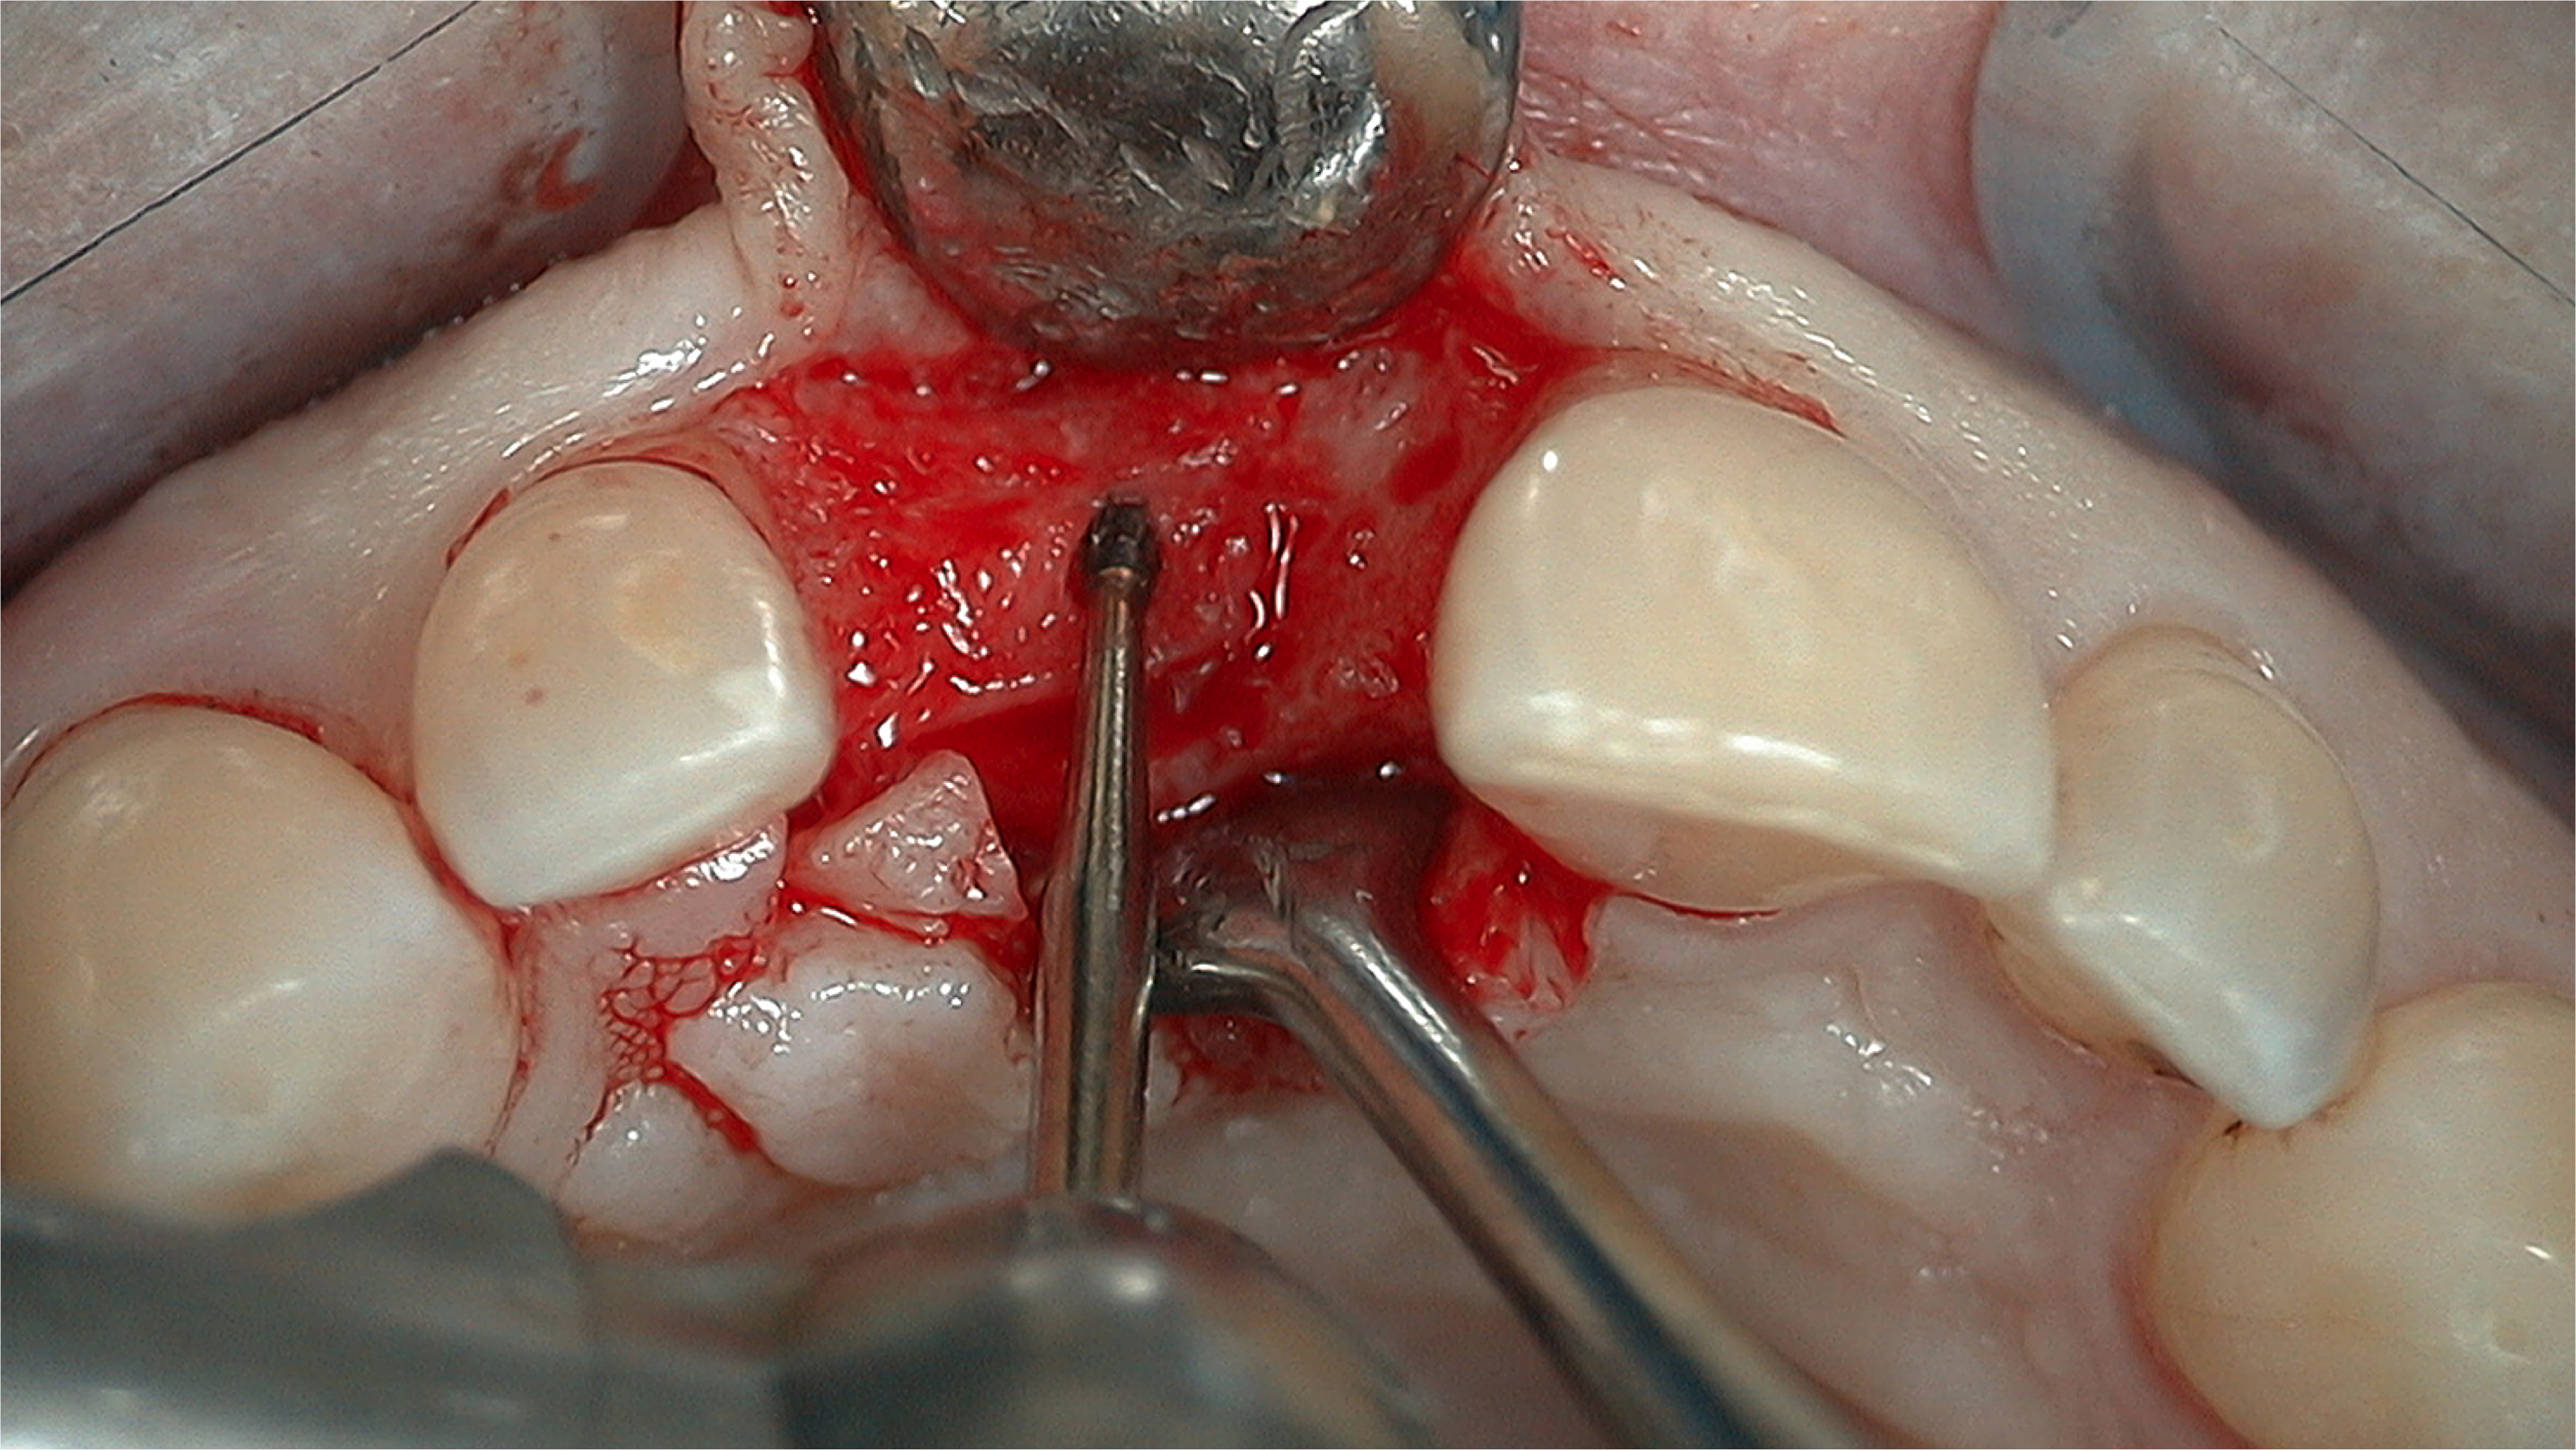

A flap procedure reveals the bone, which should be wide enough to provide 1.5 mm of bone on either side of the implant (Figure 5).6 The amount and level of bone surrounding implants is important for osseointegration, esthetics, and long-term survival.6 The location for implant placement can then be established using a round bur to place a mark in the center of the crest of bone from mesial-distally and facial-palatally (Figure 6).

Fig 5. 1.5 mm of bone should surround the implant on either side.

Figure 5

Fig 6. The location for implant placement can then be established using a round bur.

Figure 6